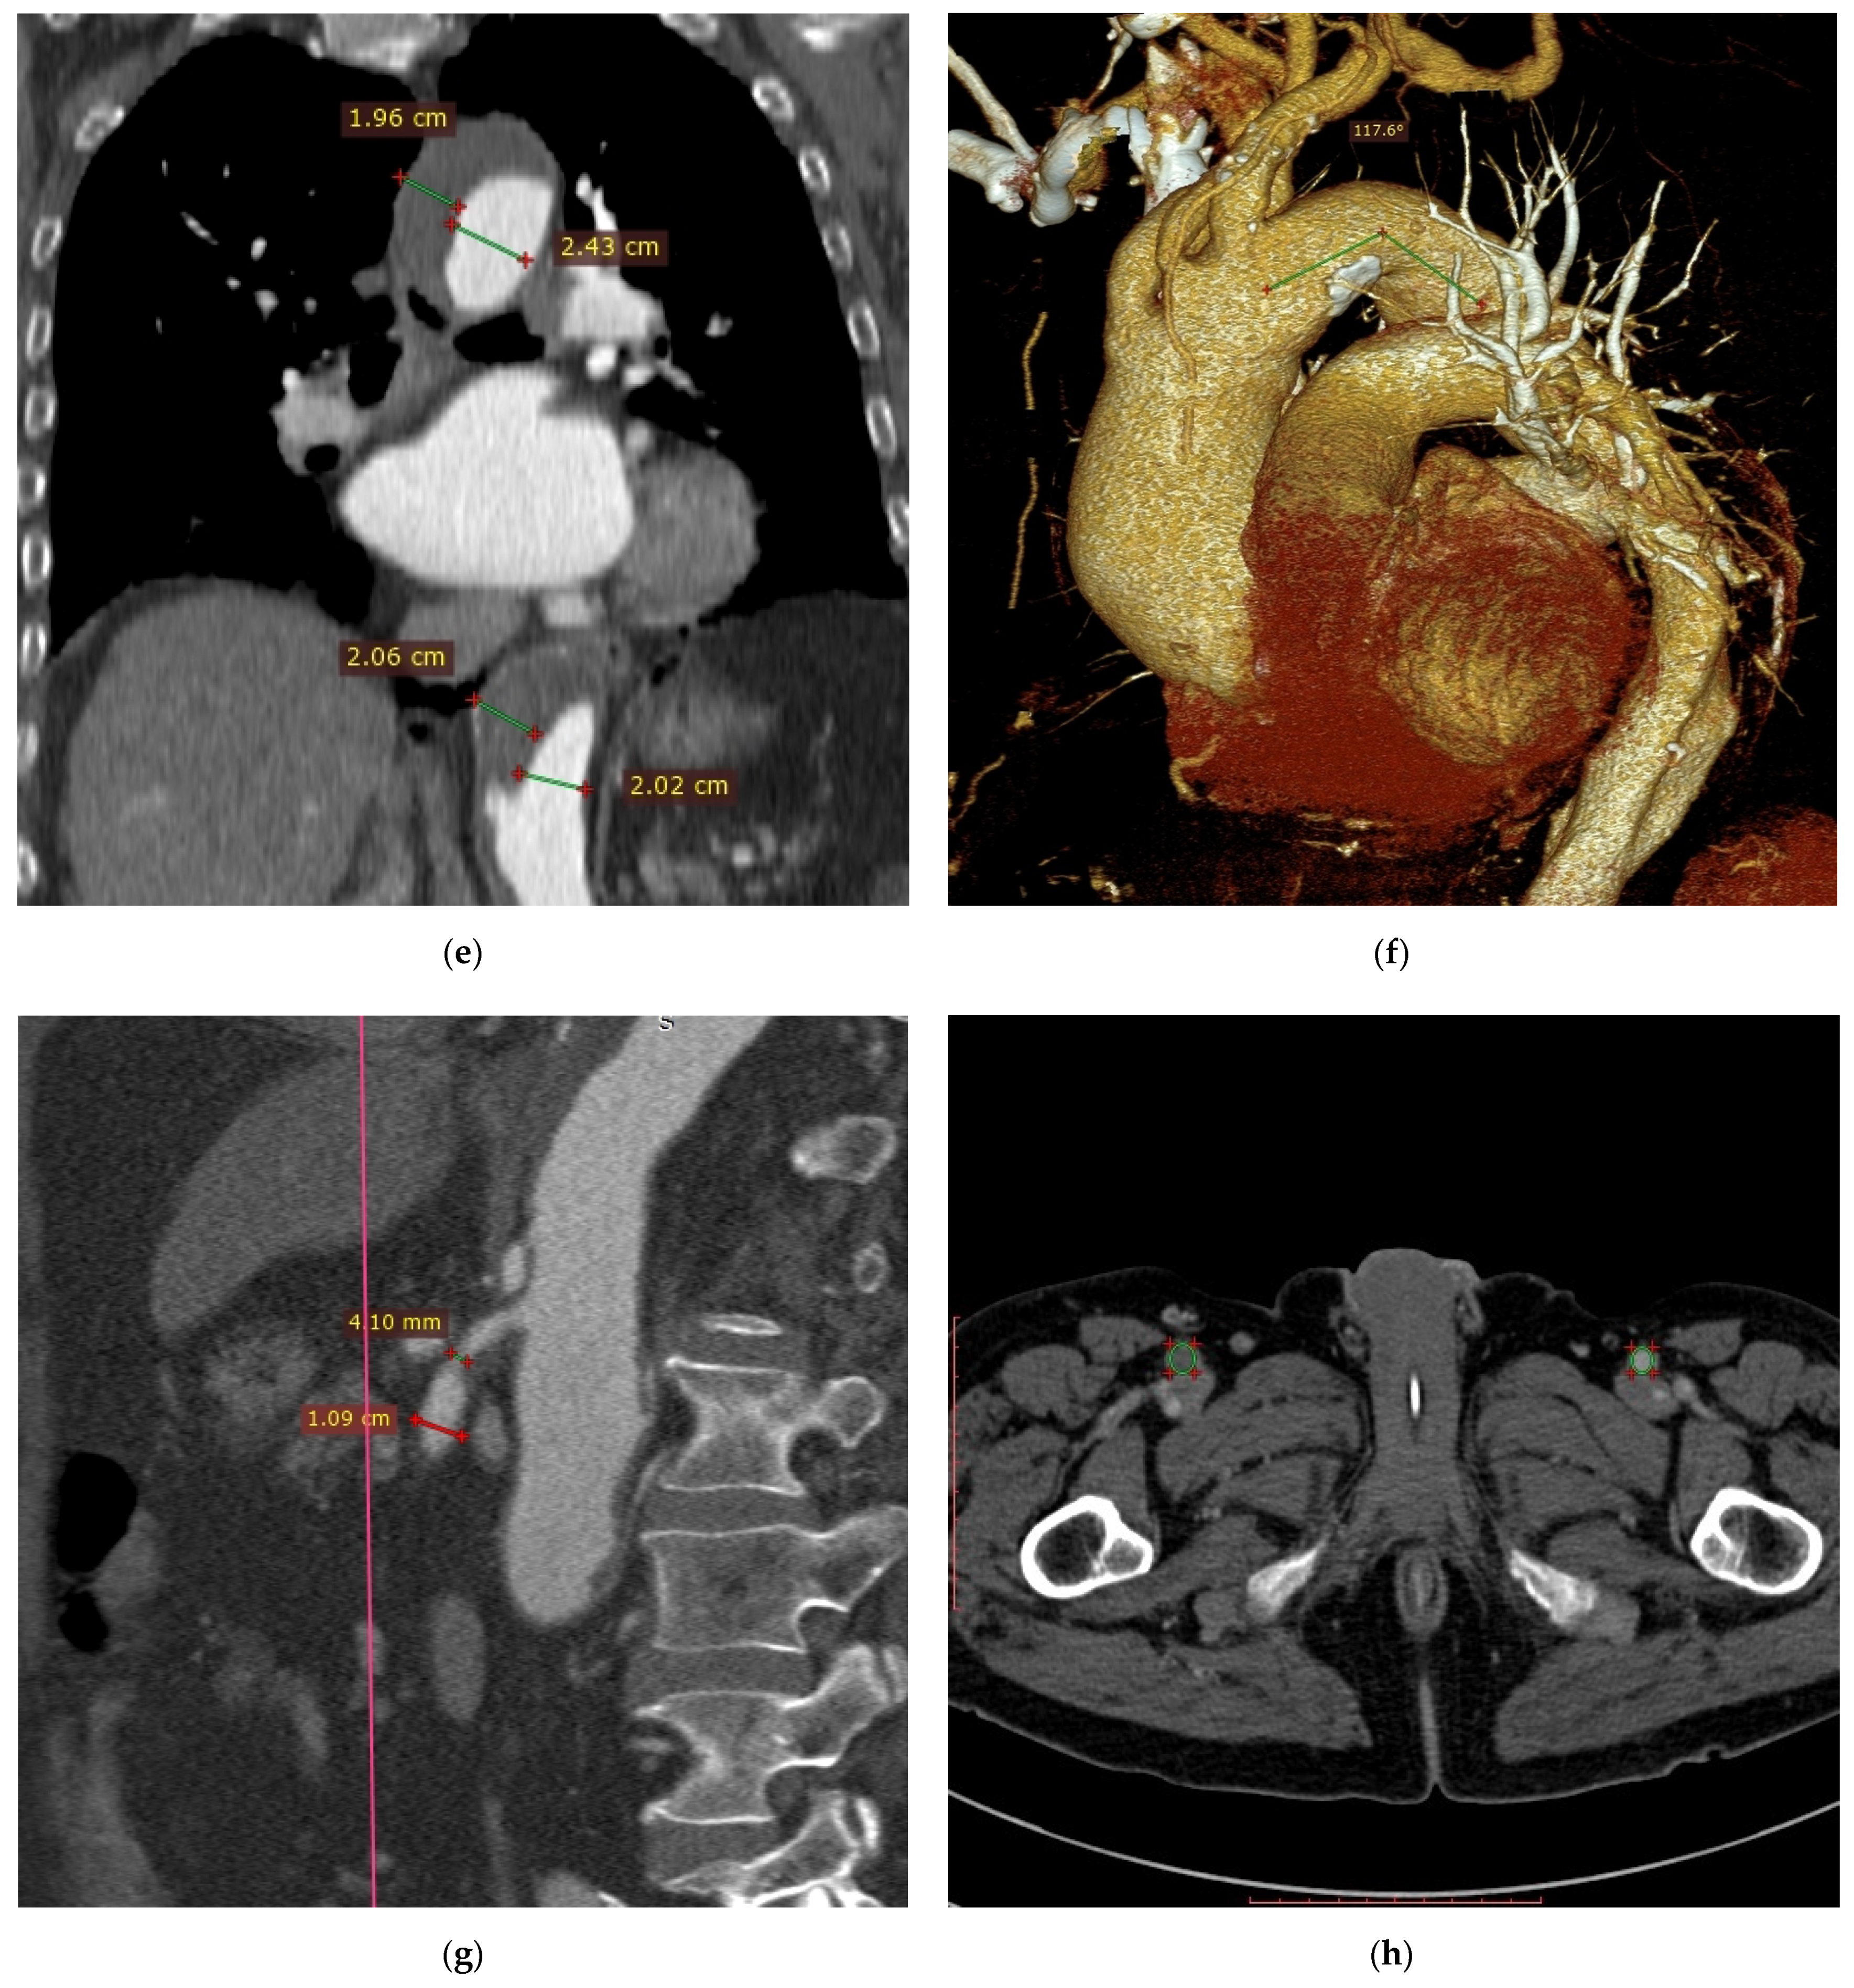

Figure 1.

Computed tomography angiography images: (a) dilation of the right and left pulmonary arteries with a borderline width of the pulmonary trunk; (b) left pulmonary artery filling defect suggesting presence of embolic material; (c) non-uniform aortic density suggesting acute aortic syndrome; (d) aneurysm of the ascending aorta, aortic arch and proximal part of the descending aorta; (e) aortic aneurysm with massive parietal thrombi/aortic aneurysm with chronic dissection and clotting of the supposedly dissected canal; (f) angular (Gothic) aortic arch; (g) stenosis of the proximal section of the superior mesenteric artery; (h) occlusion of the proximal section of the right superficial femoral artery; (i) filling defects in the veins of the right iliac axis that is most probably a thrombotic material.

On the basis of the aortic image on CTA of the pulmonary arteries and life-threatening condition, the decision was made to supplement diagnostics with CTA of the thoracic-abdominal aorta. CTA of the aorta showed aneurysm of the ascending aorta, aortic arch and proximal part of the descending aorta (maximum diameters of 6.0 cm, 3.9 cm and 4.9 cm, respectively) (Figure 1d). From the level of the left subclavian artery (LSA) origin over the further part of the thoracic aorta and proximal abdominal aorta, to the level of about 2.5 cm below the renal arteries origin, the vessel periphery revealed the presence of wide hypodense structure with thickness up to 1/2 diameter of the aortic lumen; in the proximal section, the structure was located medially and posteriorly, then left-sided and posteriorly, and in the distal section it was located both left-sided and anteriorly (Figure 1e). Regarding differentiation, the CTA image of the aorta could correspond to aortic aneurysm with massive parietal thrombi/aortic aneurysm with chronic dissection and clotting of the supposedly dissected canal. Moreover, CTA revealed angular (Gothic) aortic arch (Figure 1f), short-segment stenosis of the proximal section of the superior mesenteric artery by 50–70% of the lumen (Figure 1g), occlusion of the proximal section of the right superficial femoral artery (Figure 1h) and filling defects in the veins of the right iliac axis that is most probably a thrombotic material (Figure 1i).